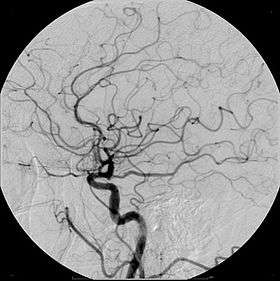

- Angiography (arterial investigations)

Organic iodine molecules used for contrast include iohexol, iodixanol and ioversol. Iodine-based contrast media are water-soluble. These contrast agents are sold as clear, colorless water solutions, with the concentration usually expressed as mg I/ml. Modern iodinated contrast agents can be used almost anywhere in the body. Most often they are used intravenously, but for various purposes they can also be used intraarterially, intrathecally (as in diskography of the spine) and intraabdominally – just about any body cavity or potential space.